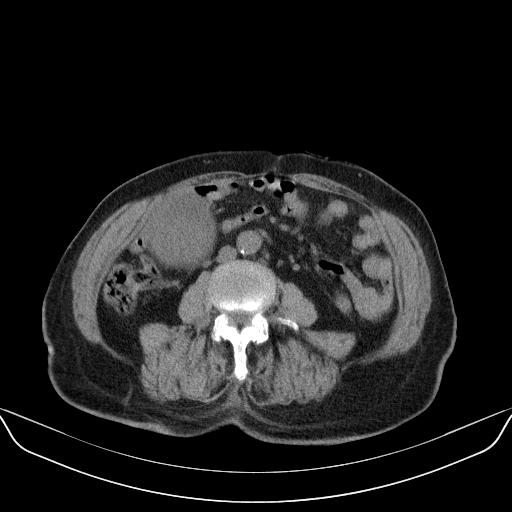

以下是引用林建春在2010-3-11 17:21:00的发言:[br]病变边界较清晰,看见明显包膜,考虑良性占位性病变。[br][br]期待病理结果!

以下是引用yuhongjun在2010-3-12 6:32:00的发言:[br]回肠末端间质瘤,不除外阑尾粘液囊腺瘤,臀部注射性肉芽肿钙化. [br] [br]